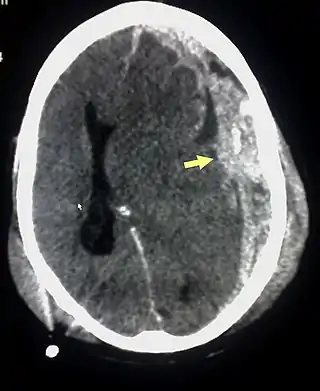

Los hematomas epidurales son los que se localizan entre la lámina interna craneal y la duramadre. Como se ha mencionado están asociados con fracturas de cráneo y ruptura de la arteria meníngea media o sus ramas. Son más comunes en las regiones parietales y temporales y son raros en las regiones frontales y occipitales. Se encuentran entre el 8% y 10% en pacientes con TCE grave. En la TAC, se ven como lesiones hiperdensas y biconvexas y debido a que no existe un espacio entre la duramadre y el hueso no suelen propagarse a menos que superen la adherencia de la duramadre. Estos hematomas son raros en infantes debido a que el cráneo es deformable lo que les confiere una protección. Además son raros en adultos mayores de 60 años debido a la adherencia débil de la duramadre al cráneo.[15]

Los hematomas subdurales se encuentran entre la cara interna de la duramadre y la superficie cerebral. Se encuentra entre el 20% y el 25% en pacientes con TCE grave. Son el resultado de hemorragia en las venas anastomóticas de la corteza cerebral superficial o ruptura de los senos venosos o sus tributarios y se asocian con daño en el tejido cerebral subyacente. Más específicamente se ha demostrado que un buen número de estos hematomas se deben a la ruptura de venas puente parasagitales[31][32]. Normalmente se expanden en la mayor parte de la convexidad cerebral pero no pueden propagarse al hemisferio contrario debido a la existencia de la hoz del cerebro. Los hematomas subdurales se clasifican en agudos, subagudos o crónicos dependiendo de la aparición y duración de estos y su aspecto característico en la TAC:[15]